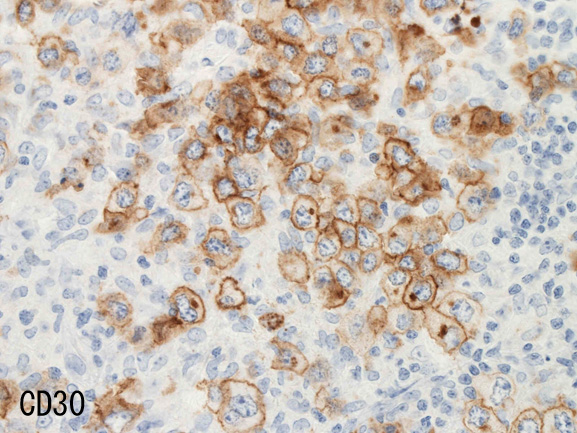

- CD30は50%に陽性。CD15は陰性。

免疫染色†

腫瘍細胞はCD20+, CD30+, CD15-, PAX-5+, Oct.2+, BOB.1+(Oct2, BOB1は田丸先生の染色結果), EBER-ISH+, EBNA2-

| CD20 | PAX-5 | CD30 | EBER-ISH+ |